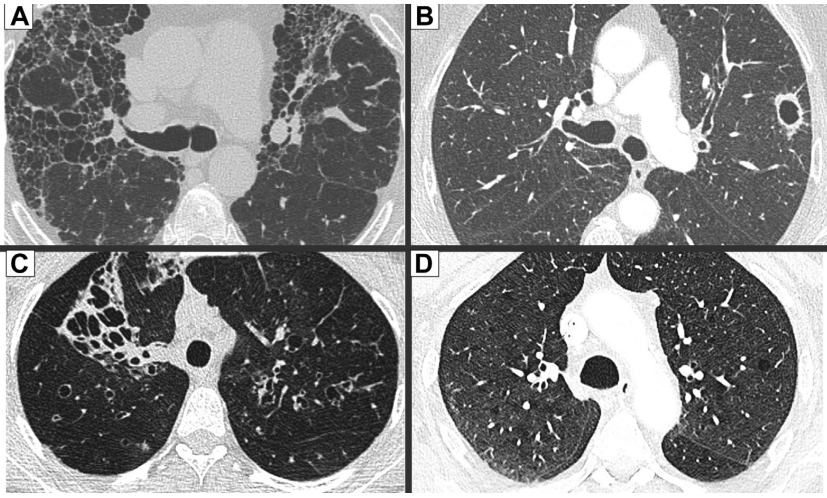

图2 A-D展示CT扫描中常见的囊性肺疾病鉴别诊断表现

(A)肺纤维化特征性的蜂窝样改变。(B)肺空洞/脓肿,可见厚壁且边界清晰,不符合典型囊肿特征。(C)囊状支气管扩张,通过连续CT层面观察气道连续性可明确诊断。(D)细微的肺小叶中心型肺气肿,通常通过缺乏明确的囊壁以及存在穿过气腔的血管来区分。